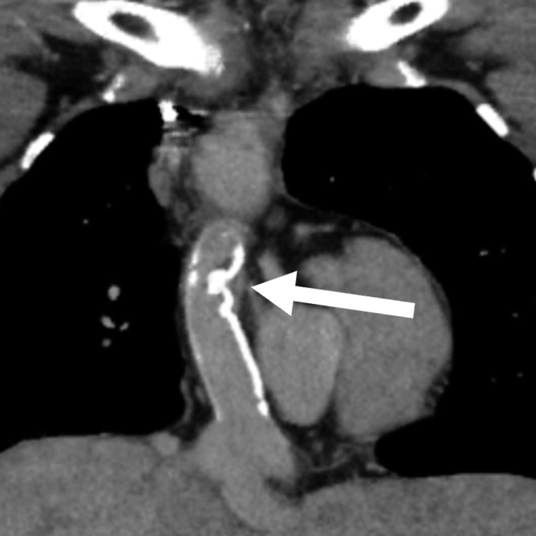

1か月健診で心雑音を指摘され,三尖弁閉鎖不全症(IIc型)と診断された.日齢41に肺動脈絞扼術を施行し,2歳4か月時に両方向性グレン手術,Damus–Kaye–Stansel(DKS)吻合,心房中隔欠損孔拡大を行った.3歳10か月時に心外導管型フォンタン手術(ePTFE: expanded polytetrafluoroethylene 20 mm)を施行した.9歳時の心臓カテーテル検査では,明らかな圧較差は認めないが,導管の一部にわずかに造影欠損を認めていた(Fig. 1).抗血栓薬は抗血小板薬のみを内服していた.19歳時に完全房室ブロックが出現し,ペースメーカー植え込みが必要となった.経胸壁心エコー検査にて中等度の新大動脈弁閉鎖不全を認め,心臓カテーテル検査・CT検査にて心外導管中央に狭窄を認め,同時手術目的に当科紹介となった.

Fig. 1 Angiography in patient 1 at 9 years of age showing a contrast defect in the extracardiac conduit in patient 1